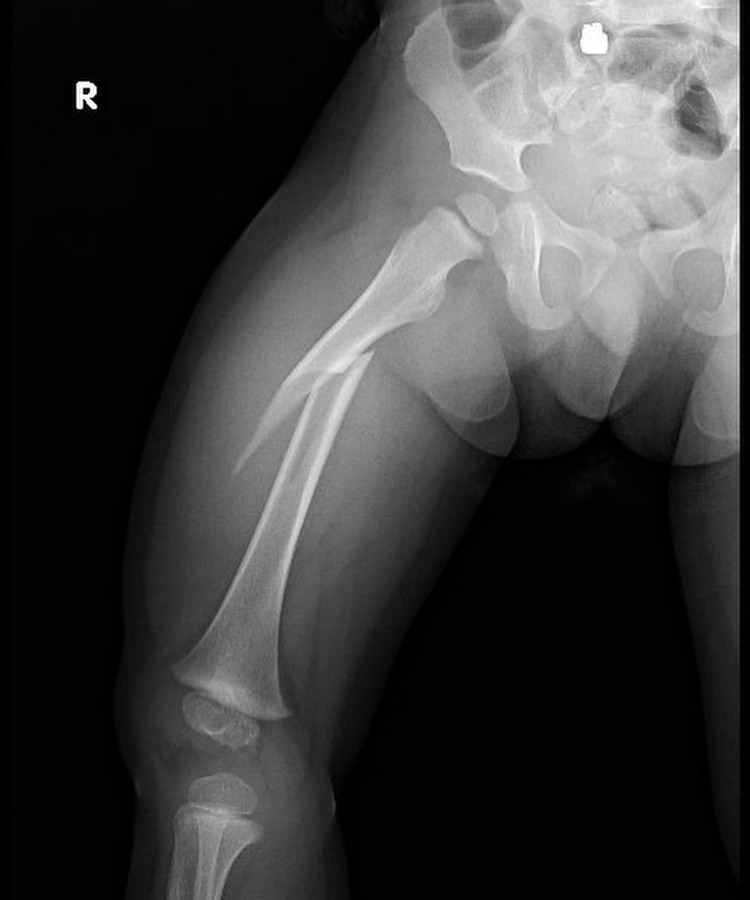

conocer másLas fracturas en niños son comunes y pueden afectar su crecimiento si no se tratan debido a las características únicas de sus huesos en desarrollo.